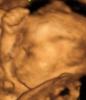

Во сколько недель лучше сделать 4д узи? Планирую идти в 26-28 недель,кто делал покажите фото ,заранее спасибо ☺️

А это в Вита Авис. Сюда вообще не советую ходить.

@alexandra_19 клиника современной медицины. Недалеко от Ашана

Врач узи в платной клинике сказала, что лучше делать с 30 до 35 недели)